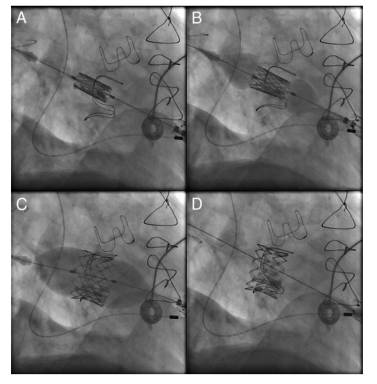

TAVR/TMVR

TAVR Device

TMVR